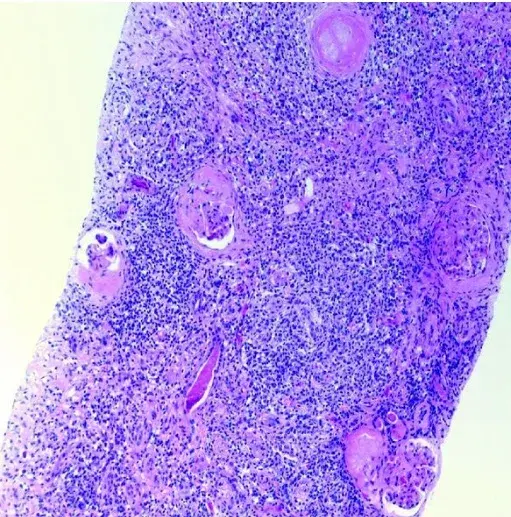

**Realizado biópsia renal** que evidenciou infiltrado intersticial intenso e difuso composto por linfócitos e plasmócitos envolvendo >70% do interstício (Figura). Identificado também fibrose estoriforme no interstício

Diante dos achados foi realizado a imunohistoquímica para IgG e IgG4 sendo evidenciado áreas focais com >10 células plasmáticas IgG4+/campo. Essa combinação de achados foi considerada consistente com o diagnóstico de **nefrite tubulointersticial relacionada a IgG4**.

Figura: Principais achados da biópsia renal para nefrite tubulointersticial relacionada a IgG-4. (A) Infiltrado denso de plasmócitos e linfócitos à microscopia de luz (coloração HE). (B) Fibrose estoriforme com aspecto de “cartwheel” é observada na microscopia de luz (coloração HE). (C) Células positivas para IgG4 são observadas em mais de 10 células por campo (imunohistoquímica para IgG4).

Os achados patológicos incluem um **infiltrado linfoplasmocitário**, **fibrose estoriforme**, **flebite obliterante** e **infiltrados de plasmócitos IgG4+**.

- A histologia revela um infiltrado intersticial linfoplasmocítico dominante com marcação para IgG4. Fibrose estoriforme e flebite obliterativa podem ser observadas.